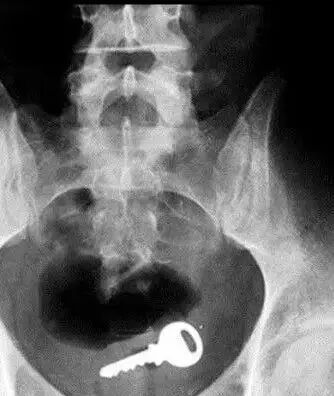

还有人开门,姿势太投入,一屁股坐进钥匙(我也不懂),现场目击者从嗑瓜子到集体失语……